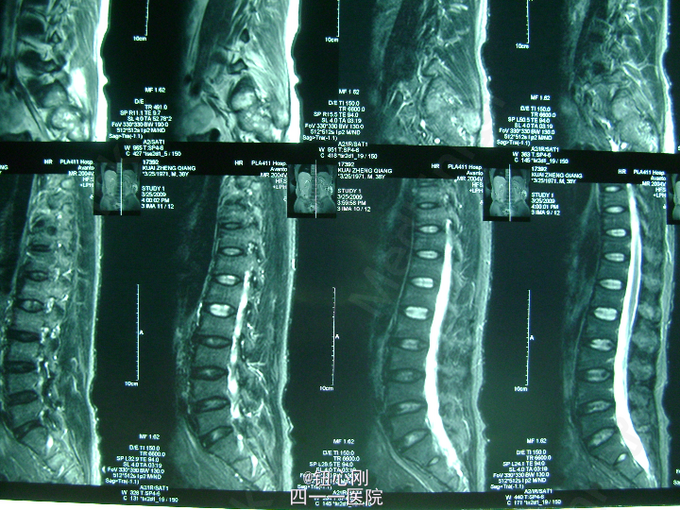

男,38岁,主诉全身多处骨关节疼痛5年。5年内身高降低5厘米,活动后全身关节疼痛加重,休息后减轻。疼痛以腰椎,全身大关节为主。既往体健,否认有肾功能不全及胃肠道病史,肝胆胰腺病史,无激素及其他特殊药物使用史。无毒物接触史。饮食正常,家族中无类似病史

查体间:略有驼背畸形,全身大关节及脊柱活动性降低,大关节处有明显叩压痛。 辅助检查:三大常规,肝肾功正常,血沉正常,各肿瘤指标正常,钙正常,血磷减低(0.44mmol/L),骨特异性碱性磷酸酶升高(99.95ng/L),PTH、CT正常,尿本周蛋白(-),血清蛋白电泳正常,无M蛋白,血皮质醇正常。 胸片,心电图,肝胆胰脾双肾B超正常。

病史特点:1、壮年男性,以全身多处骨痛为主,伴身高降低为主诉;2、体检可见:驼背畸形,脊柱及四肢大关节处活动降低,有叩压痛;3、辅助检查提示:血磷减低,血钙正常,影像学显示:全身骨骼骨质疏松改变,未见其它骨破坏。 鉴别诊断:排除骨髓瘤,转移性肿瘤,甲状旁腺亢进,肾性骨病,原发性及药物性骨质疏松 诊断:成人低磷性骨软化症 治疗:予以钙片、骨化三醇,中性磷酸盐口服